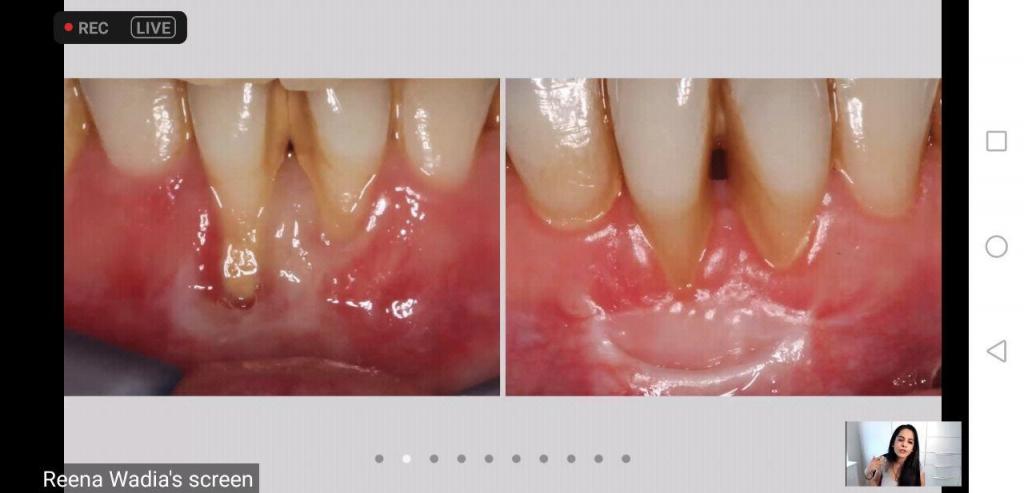

اقامت كلية طب الأسنان في جامعة الموصل محاضرة علمية عن طب اللثة و ما حول الأسنان ،يوم الأربعاء الموافق السادس من آب ٢٠٢٠، استضافت فيها الدكتورة رينا واديا / اختصاص اللثة / قسم ترميم الأسنان/ جامعة الملك في لندن/ المملكة المتحدة ، حيث القت محاضرة قيمة عن أساسيات طب و جراحة اللثة و ما حول الأسنان، عبر الفضاء الالكتروني ، حضرها عدد من السادة عمداء كليات طب الأسنان في العراق و رؤساء الأقسام و أطباء الأسنان و الطلبة .

تناولت المحاضرة أهم العوامل التي تؤثر في صحة اللثة مثل الأمراض المزمنة و التدخين و العادات الصحية السيئة، و التصنيفات الحديثة لأمراض اللثة، و محاور أخرى، كما أجابت عن أسئلة الحضور.